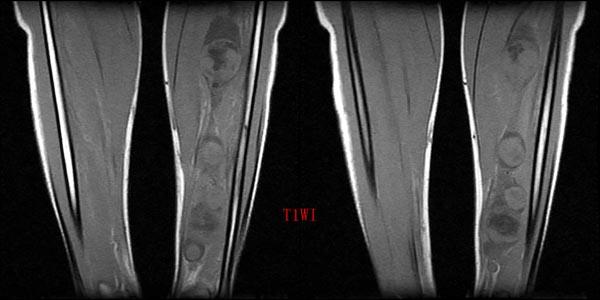

腿部核磁共振

腿部核磁共振,核磁共振内部

mri0011:小腿占位

腿部核磁共振图片